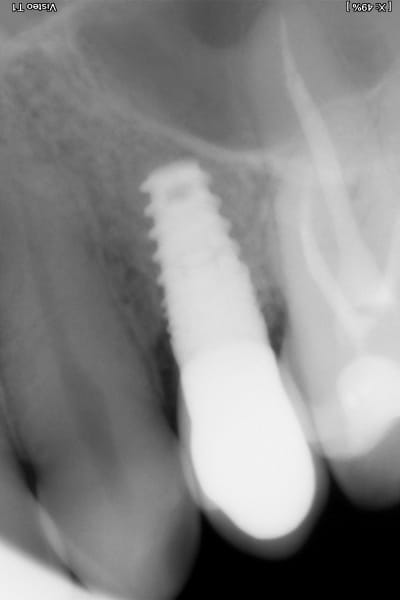

Zubní implantát je alternativním protetickým řešením, neboť chybějící zuby lze kromě klasického můstku klinicky vhodněji nahradit zubním implantátem, který splňuje všechny funkce původního zubu a navíc je jeho přirozenou a věrnou kopií, bez nutnosti zbrousit (degradovat) jiné okolní zuby (jako v případě můstku).